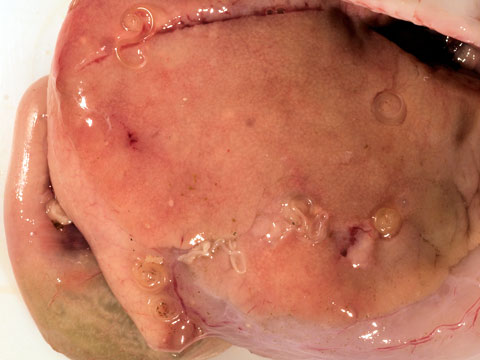

L’ anisakis è un nematode (verme) parassita che si annida nelle pareti dello stomaco. Se però il pesce non viene eviscerato immediatamene, può passare facilmente nella carne e nei fasci muscolari quindi diventa molto difficile riuscire a vederlo. Sushi: dilagante moda culinaria, ma anche possibile minaccia per la salute.

Il parassita adulto vive nello stomaco dell’ospite e produce uova, che immesse di nuovo nell’acqua con le feci danno inizio ad un nuovo ciclo. Alcuni prodotti ittici possono essere infestati dall’ anisakis , un parassita che può causare disturbi gastrointestinali gravi.